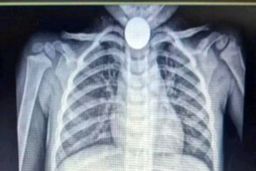

والدین کودک سه ساله که متوجه بلع سکه توسط کودکشان شده بودند با اقدام سریع او را به بیمارستان منتقل می کنند.